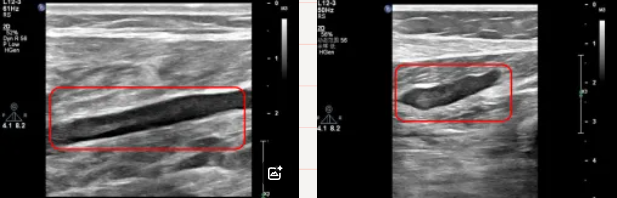

血管超声:诊断静脉曲张“金标准”

血管超声(彩色多普勒超声)评估静脉曲张精准、无创,不仅能观察血管形态,还能实时监测血流动态。

患者站立或平躺,医生在腿部涂抹耦合剂,用高频探头扫描;

通过彩色多普勒技术,血流信号以红蓝两色显示(颜色表示方向,红色朝向探头,蓝色背离探头),直观判断病变位置。